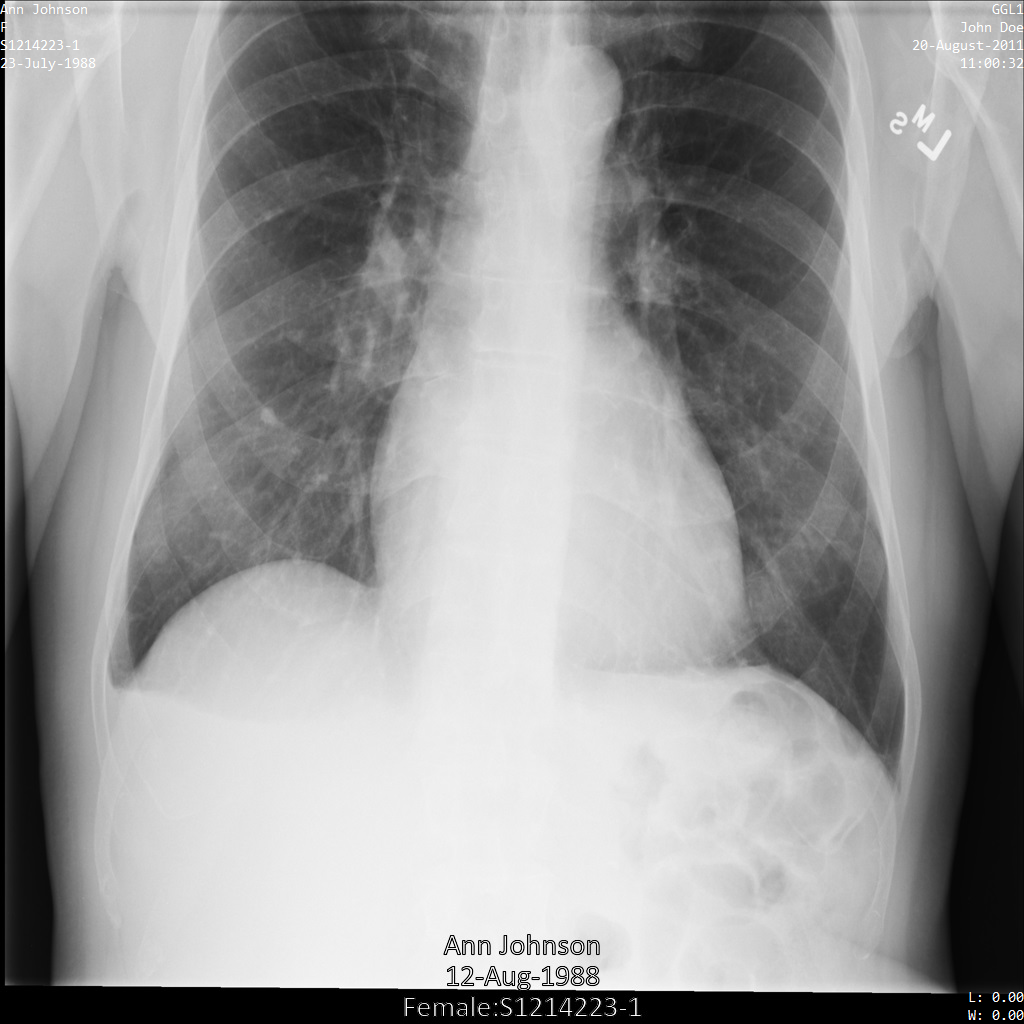

다음 각 섹션에서는 다양한 방법을 사용하여 DICOM 데이터를 익명화하는 방법을 설명합니다. 익명화된 이미지의 출력은 각 샘플에 제공됩니다. 각 샘플은 다음과 같은 원본 이미지를 입력으로 사용합니다.

각 익명화 작업의 출력 이미지를 이 원본 이미지와 비교하여 작업의 효과를 확인할 수 있습니다.

Cloud Healthcare API에 이미지를 제출하면 이미지가 다음과 같이 표시됩니다. 이미지 상단 모서리에 표시되는 메타데이터가 수정되었지만 이미지 하단에 있는 번인 보호 상태 정보(PHI)는 유지됩니다. 번인 텍스트도 삭제하려면 이미지에서 번인 텍스트 수정을 참조하세요.

REST